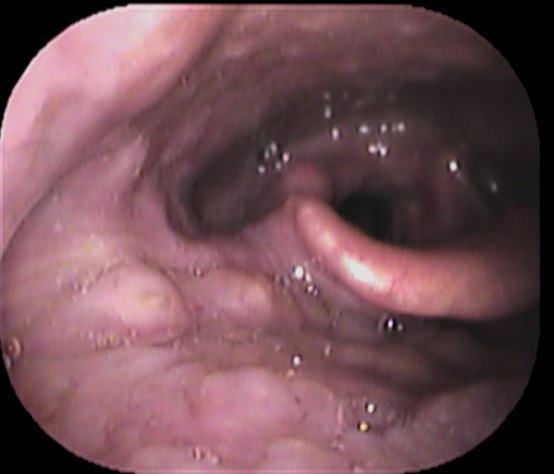

まずは喉を診てみます。

見える範囲には異常を認めませんでした。

続いてファイバーで奥をチェックします

声帯の一部に白い隆起がありました。

どれかと言いますと↓

赤丸部分です。

逆流性食道炎のアンケート結果が高値で、逆流性食道炎が原因の喉頭肉芽腫と診断しました。

喉頭肉芽腫とは、慢性的な刺激が原因で声帯の後方の粘膜が炎症を起こし、白く隆起する疾患です。

逆流性食道炎が原因で声帯後方の粘膜が白く隆起したと考えられます。

逆流性食道炎の治療薬で、白い隆起は縮小していきました。

「喉違和感」「詰まった感じ」がある方は、耳鼻咽喉科の受診をおススメいたします